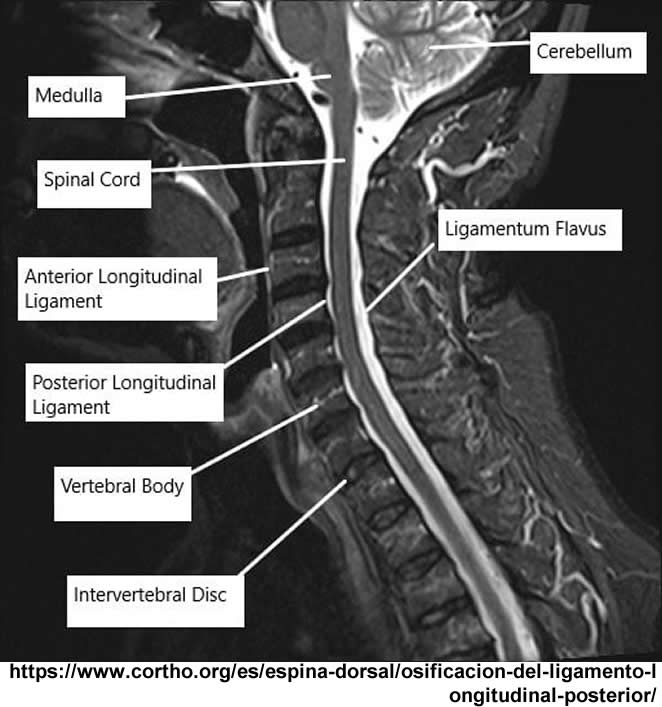

Se observa hipo intensidad del ligamento longitudinal anterior y posterior de la columna cervical, también se observa perdida de la movilidad y rigidez de la misma, los ligamentos interespinosos se ven hipointensos en T2 y en T1, al igual que el pliegue nucal, lo que sugiere calcificación de estas estructuras anatómicas.

Se observa fusión de las vertebras cervicales 5-6 y 6-7, dando la apariencia de bambú.

Dentro del estudio imagenológico con diferentes técnicas, es importante mencionar que es de utilidad un protocolo específico para espondiloartropatías en el caso de RM, ya que se busca detectar edema de estructuras afectadas, siendo un protocolo útil en la evaluación de la columna vertebral la secuencia ponderada en T1 TSE junto a una secuencia de inversión-recuperación de tiempo corto (STIR). Debe ser empleada una matriz de 512 pixeles, con un grosor de corte de 3 a 4mm, adquirida con un resonador de 1,5Tesla. La administración de gadolinio asociada a secuencias con saturación grasa T1 turbo spin eco se requieren para una mejor evaluación de algunos aspectos, como por ejemplo la entesitis, según la experiencia de algunos autores, al igual que la evaluación de abscesos asociados a la espondilodiscitis séptica, para la evaluación de tejido necrótico, ver la extensión de masa de partes blandas y el realce discal. También son útiles las secuencias STIR, particularmente en la evaluación de articulaciones costovertebrales.